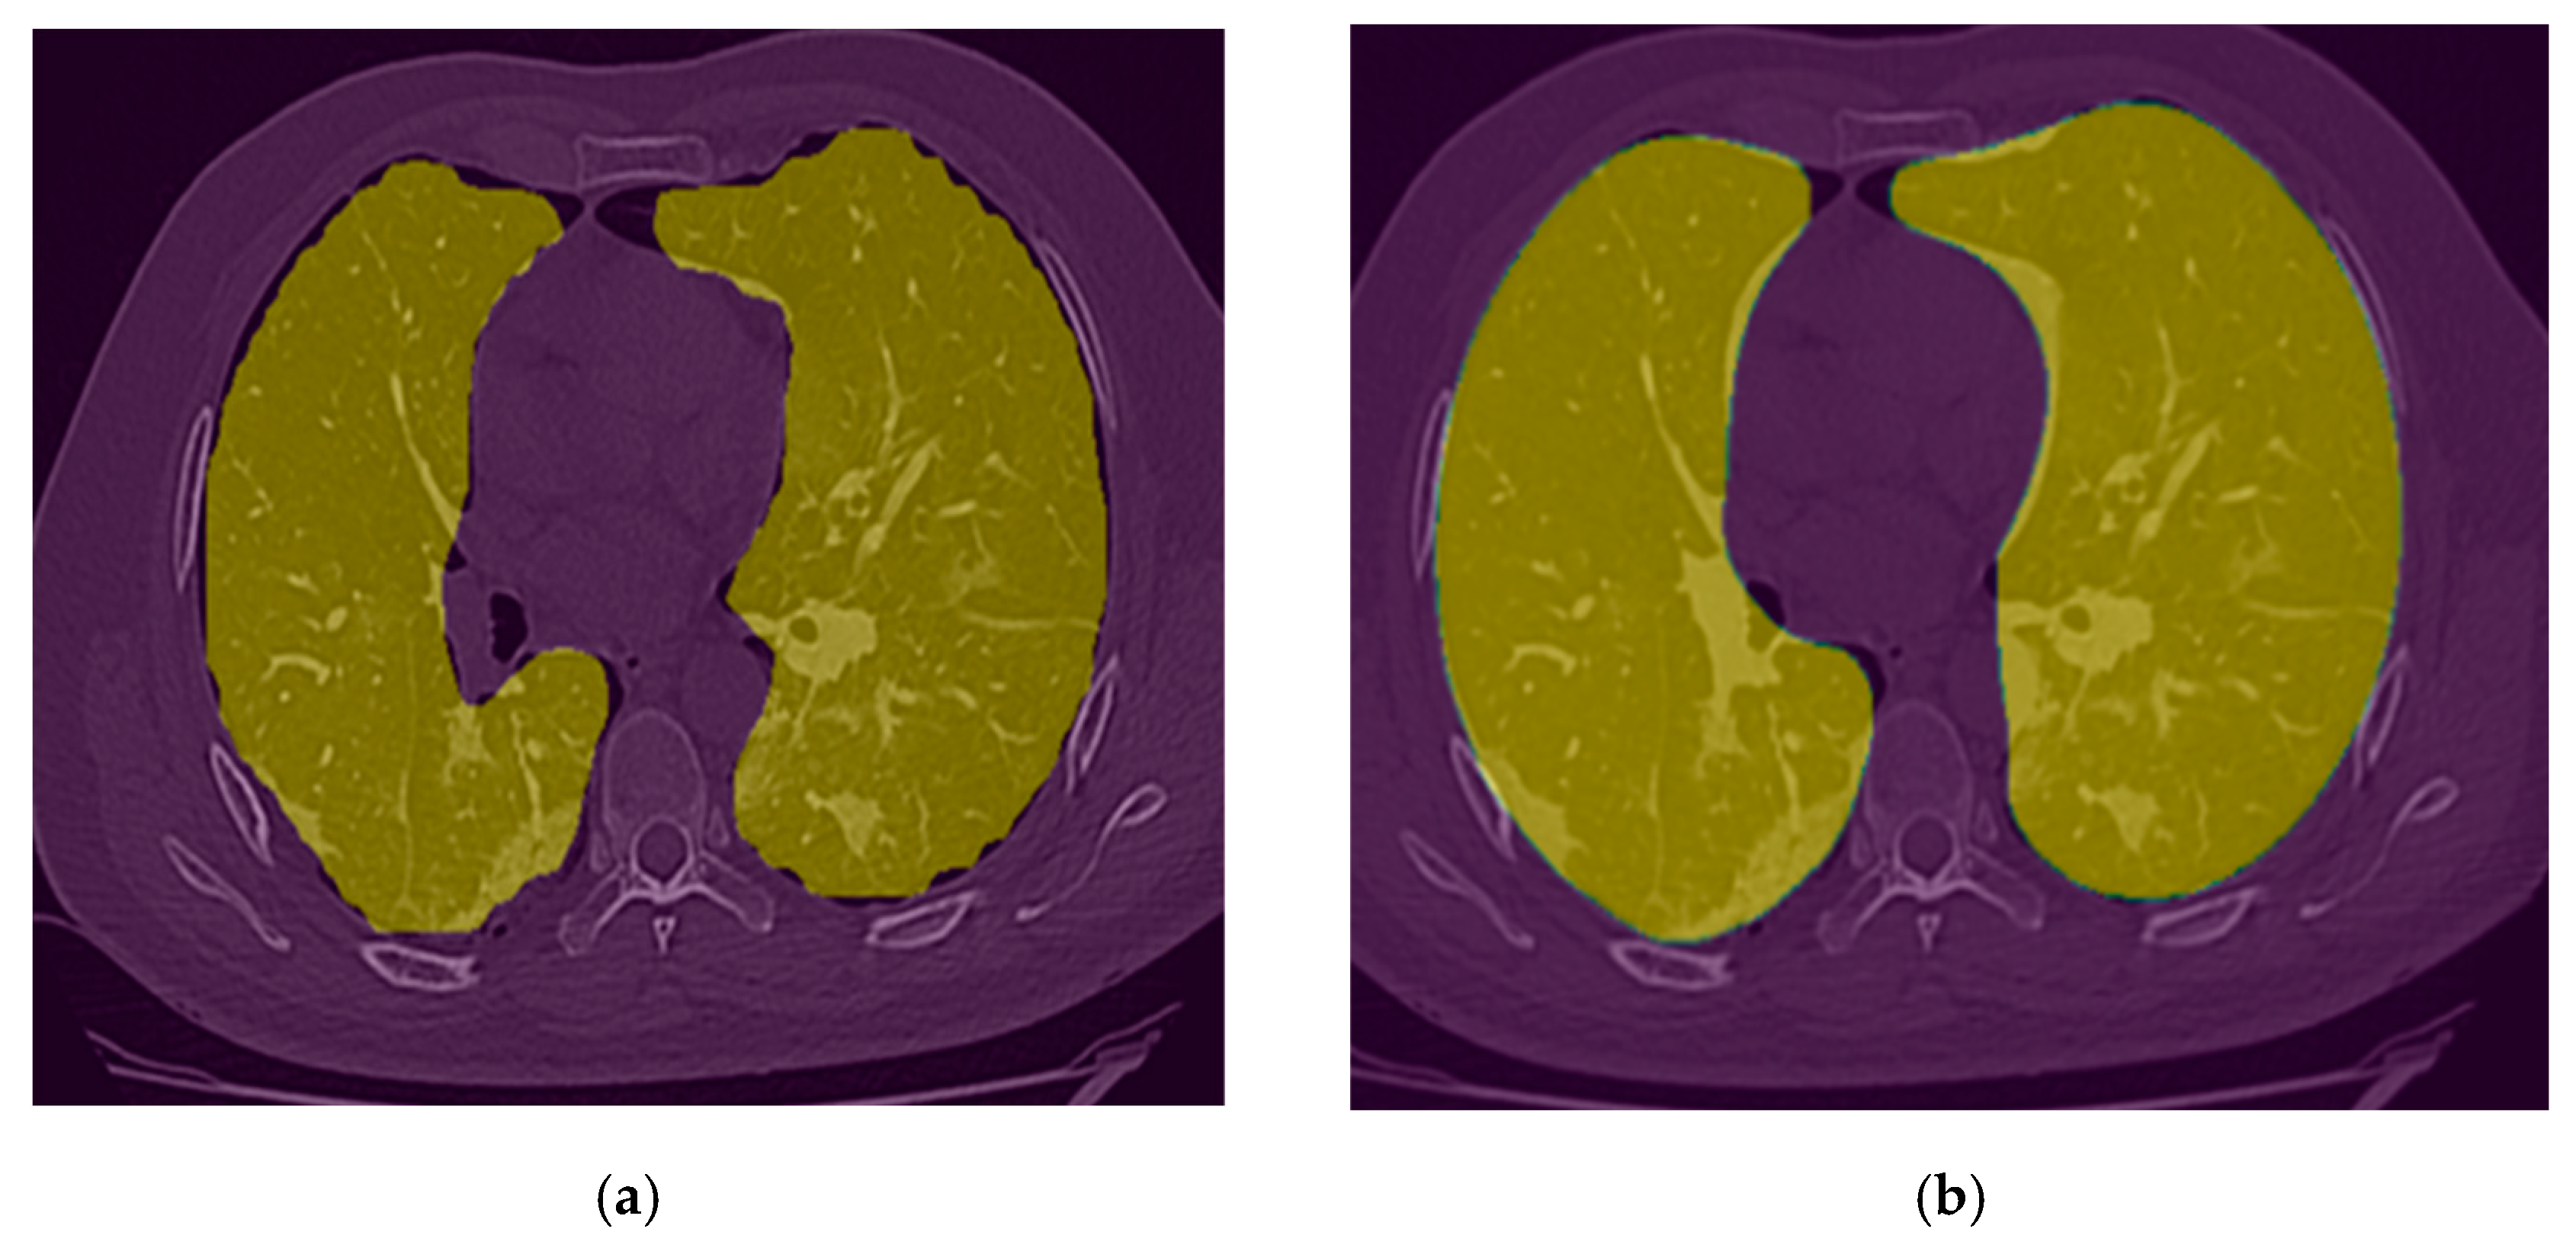

2.3.1. Lung Segmentation

2.3.2. Infection Area Segmentation

2.4. Image Postprocessing and Correction